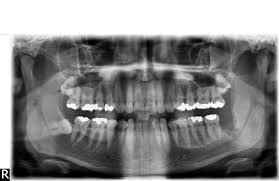

Häufig verläuft ein Nerv entweder durch die Wurzeln oder am Zahn entlang. Und bei nicht wenigen war es der fall dass der eingriff nah am nerv vorgenommen wurde das risiko also da war. Bevor ich meinen körper über jahre mit schmerzmitteln schädige und schmerzen leide würde ich mich diesem eingriff unterziehen.

Sie liegen sehr nah am Nerv weshalb der Arzt nur zwei auf Einmal zieht. Bei der lokalen Narkose besteht das Risiko vor allem dadurch dass durch die Nadel ein Nerv beschädigt wird.